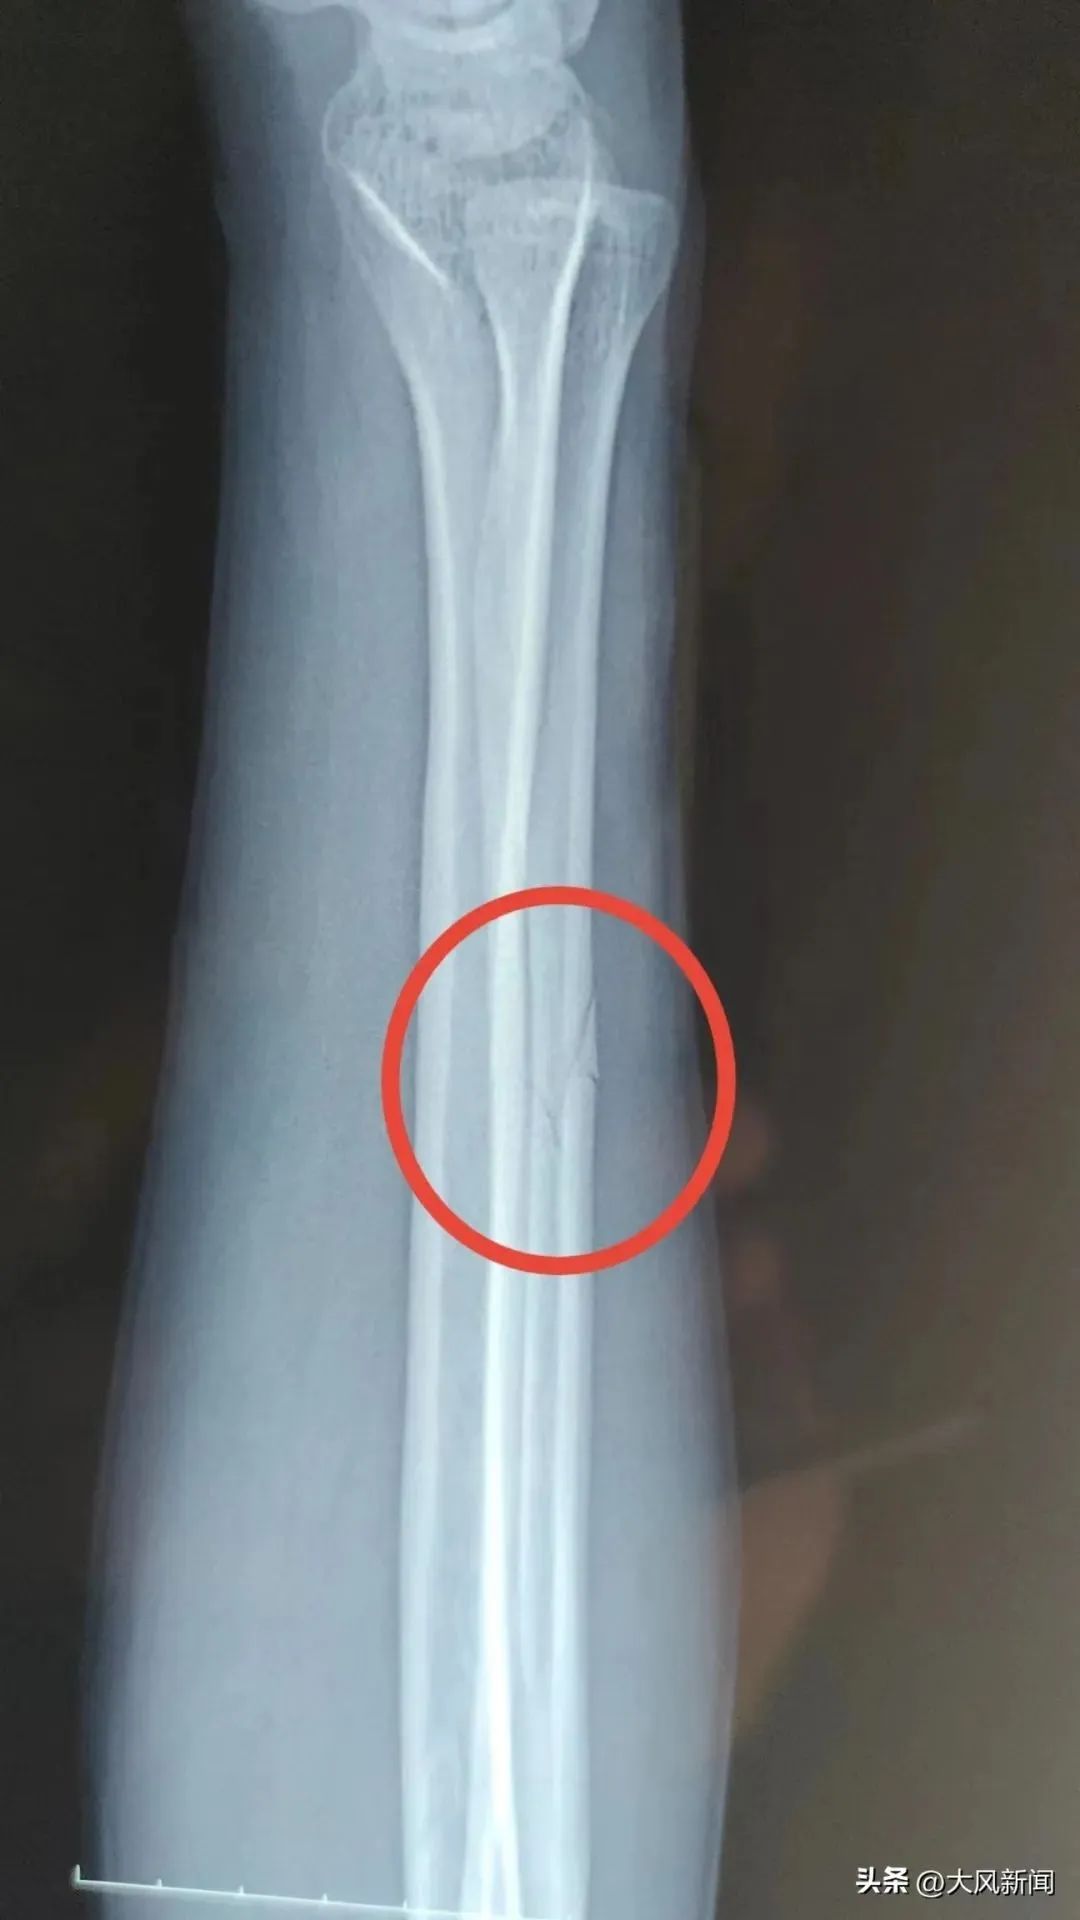

事发后宋某报了警,当晚去医院检查并打了石膏,医生让先回家观察。宋某系第二天右臂痛疼难忍,于2022年11月13日下午6时自行前往丹凤县医院检查。经诊断右尺骨骨折,外伤性头疼。